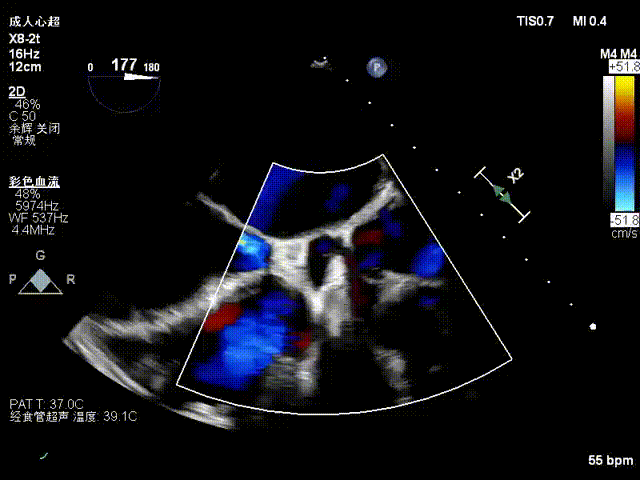

术前超声

重度三尖瓣反流(4+)。